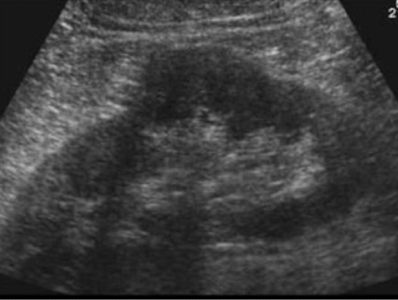

What portion of the kidney is this that looks like a donut

upper & lower poles in transverse